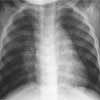

Right upper lobe consolidation is evident in this chest film from a 2-year-old girl who had an abrupt onset of fever, chills, productive cough, and right-sided abdominal pain. Based on the patient’s workup and response to therapy, the probable diagnosis was streptococcal pneumonia.

Image courtesy of Suzanne M. Lassieur, MD and Richard F. Jacobs, MD.